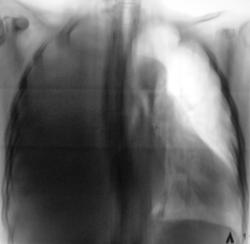

До и после пункции.

Левосторонний посттравматический плеврит.

До и после пункции.